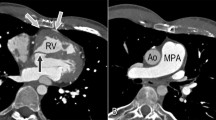

CT is crucial in investigating PAH associated with congenital heart disease, providing detailed information on cardiac chambers, great arteries, pulmonary vasculature, parenchyma, and mediastinal structures in a single acquisition with high spatial resolution (Fig. 3a). This is particularly beneficial when acoustic windows are limited (constraining echocardiography), in case of lung disease, or when patients cannot undergo MRI. Communication between chambers can be visualized, and shunt direction can be inferred from the contrast flow. CTPA is the preferred noninvasive method for evaluating proximal and distal PAs, identifying PA dilation and in-situ thrombus formation due to sluggish blood flow. CT excels in assessing extracardiac features, notably native or surgically created systemic-to-pulmonary shunts [53].

Heart CT findings in pulmonary hypertension. a 3D volume rendering image of the heart and pulmonary vessels showing adulthood-discovered congenital malformation with inferior vena cava draining into the left atrium (LA). b LA enlargement. How to measure the LA anteroposterior diameter is reported (double-sided arrow). c Left coronary artery calcification (arrow). d. Aortic valve calcification (arrow)